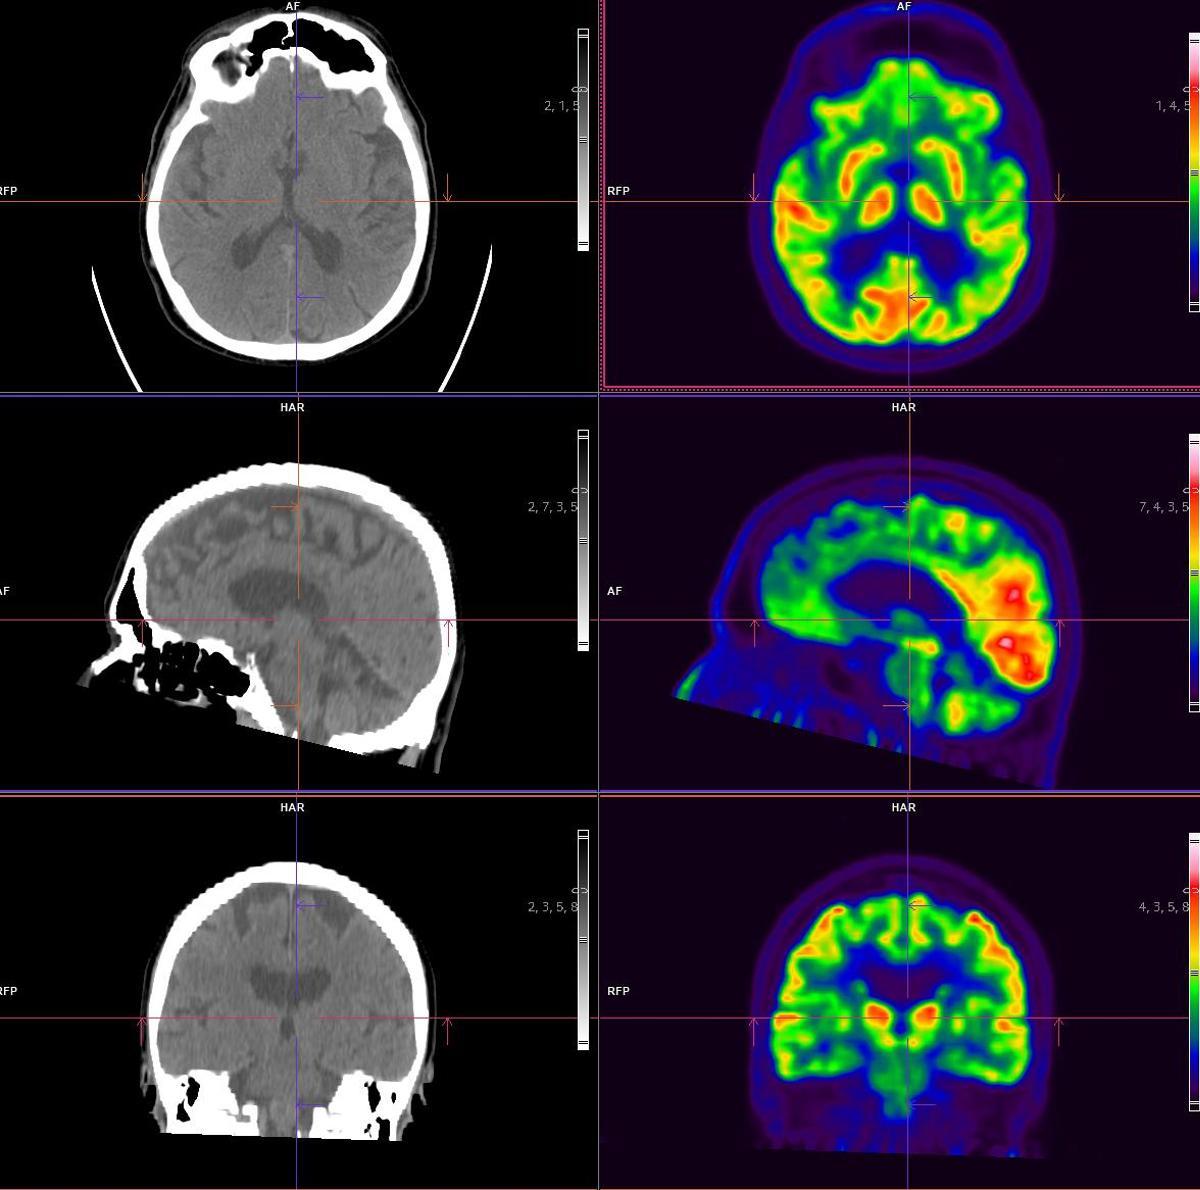

Eine PET-CT-Untersuchung vereint in einem einzigen Verfahren zwei komplementäre Techniken. Die Computertomografie (CT) erzeugt Schnittbilder der inneren Körperstrukturen, die zusammengesetzt ein dreidimensionales Abbild des Organismus ergeben. Die Positronen-Emissions-Tomografie (PET) wiederum liefert Informationen über die Organfunktion und macht mögliche zelluläre Veränderungen erkennbar. Die Verknüpfung metabolischer und anatomischer Daten ermöglicht es den Fachärztinnen und Fachärzten, zahlreiche Erkrankungen bereits früh zu diagnostizieren und beispielsweise das Stadium und die Ausprägung von Tumoren oder neurodegenerativen Prozessen präzise zu bestimmen. Es gilt als wissenschaftlich nachgewiesen, dass Tumorzellen für ihren Stoffwechsel deutlich größere Mengen an Glukose benötigen, da sie aufgrund ihres schnelleren Wachstums wesentlich mehr Energie verbrauchen als gesunde Zellen.

Nach diesem Prinzip erhält die Patientin oder der Patient in den meisten Untersuchungen ein Radiopharmakon, das Glukose enthält und die Eigenschaft besitzt, beim Eindringen in die Zellen Lichtphotonen zu erzeugen. Diese Lichtsignale werden im PET-CT sichtbar gemacht und ermöglichen so die Darstellung der zellulären Aktivität. Auf diese Weise lässt sich der Glukoseverbrauch derjenigen Zellen erfassen, die das Gewebe und die Organe des Körpers bilden. Wie beschrieben, konzentriert sich die Substanz wenige Minuten nach der Injektion in jenen Körperregionen, in denen eine erhöhte metabolische oder biochemische Aktivität – also ein gesteigerter Glukoseverbrauch – besteht. Wird in bestimmten Geweben ein ungewöhnlich hoher Verbrauch des Radiopharmakons beobachtet, deutet dies darauf hin, dass dort eine tumoröse, infektiöse oder neurodegenerative Erkrankung vorliegen könnte.

Der Leistungsumfang des PET-CT ermöglicht nun zusätzliche diagnostische Untersuchungen. Hauptsächlich wird das Gerät für die Diagnose und die Verlaufsbeurteilung onkologischer Erkrankungen eingesetzt, insbesondere bei Lungen-, Brust-, Haut-, Magen-Darm-, Knochen- und Prostatakrebs. Das digitale PET-CT ist jedoch mittlerweile auch die Referenzmethode für die Diagnose neurodegenerativer Erkrankungen wie Alzheimer und anderer Demenzen. Zudem ermöglicht die Einführung neuer Radiopharmaka wie Beta-Amyloid eine präzisere Abgrenzung gegenüber weiteren neurodegenerativen Erkrankungen wie Parkinson, MSA oder CBS.